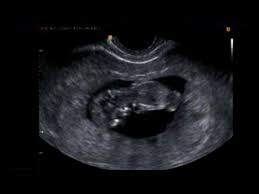

A partir de la semana 11 cuando el feto mide entre 45 y 84 milímetros ya se realiza la ecografía de cribado de alteraciones cromosómicas y de alteraciones anatómicas mayores. Con apenas 12 semanas de embarazo este bebé ya cuenta con todas las estructuras corporales básicas que podrán verse en el momento del nacimientoEs un ser humano completo que podemos contemplar en ecografía 4DLo que le falta es tiempo de maduración para que todos sus órganos logren completar su desarrollo y la proporcionalidad entre la cabeza y las. En la semana 11 de gestación el feto mide alrededor de 4 cm desde la cabeza al coxis.

La cabeza representa la mitad de su longitud como se aprecia en esta silueta de perfil de una ecografía en 2D. Tu cuerpo en la semana 11 de embarazo gemelar. Te explicamos cómo evoluciona tu cuerpo a las 11 semanas de embarazo y cómo va creciendo tu bebé.

Ecografía en 2D y 3D de embarazo de 111 semanas. En la semana 11 de embarazo tu bebé comenzará a formar sus órganos sexuales.